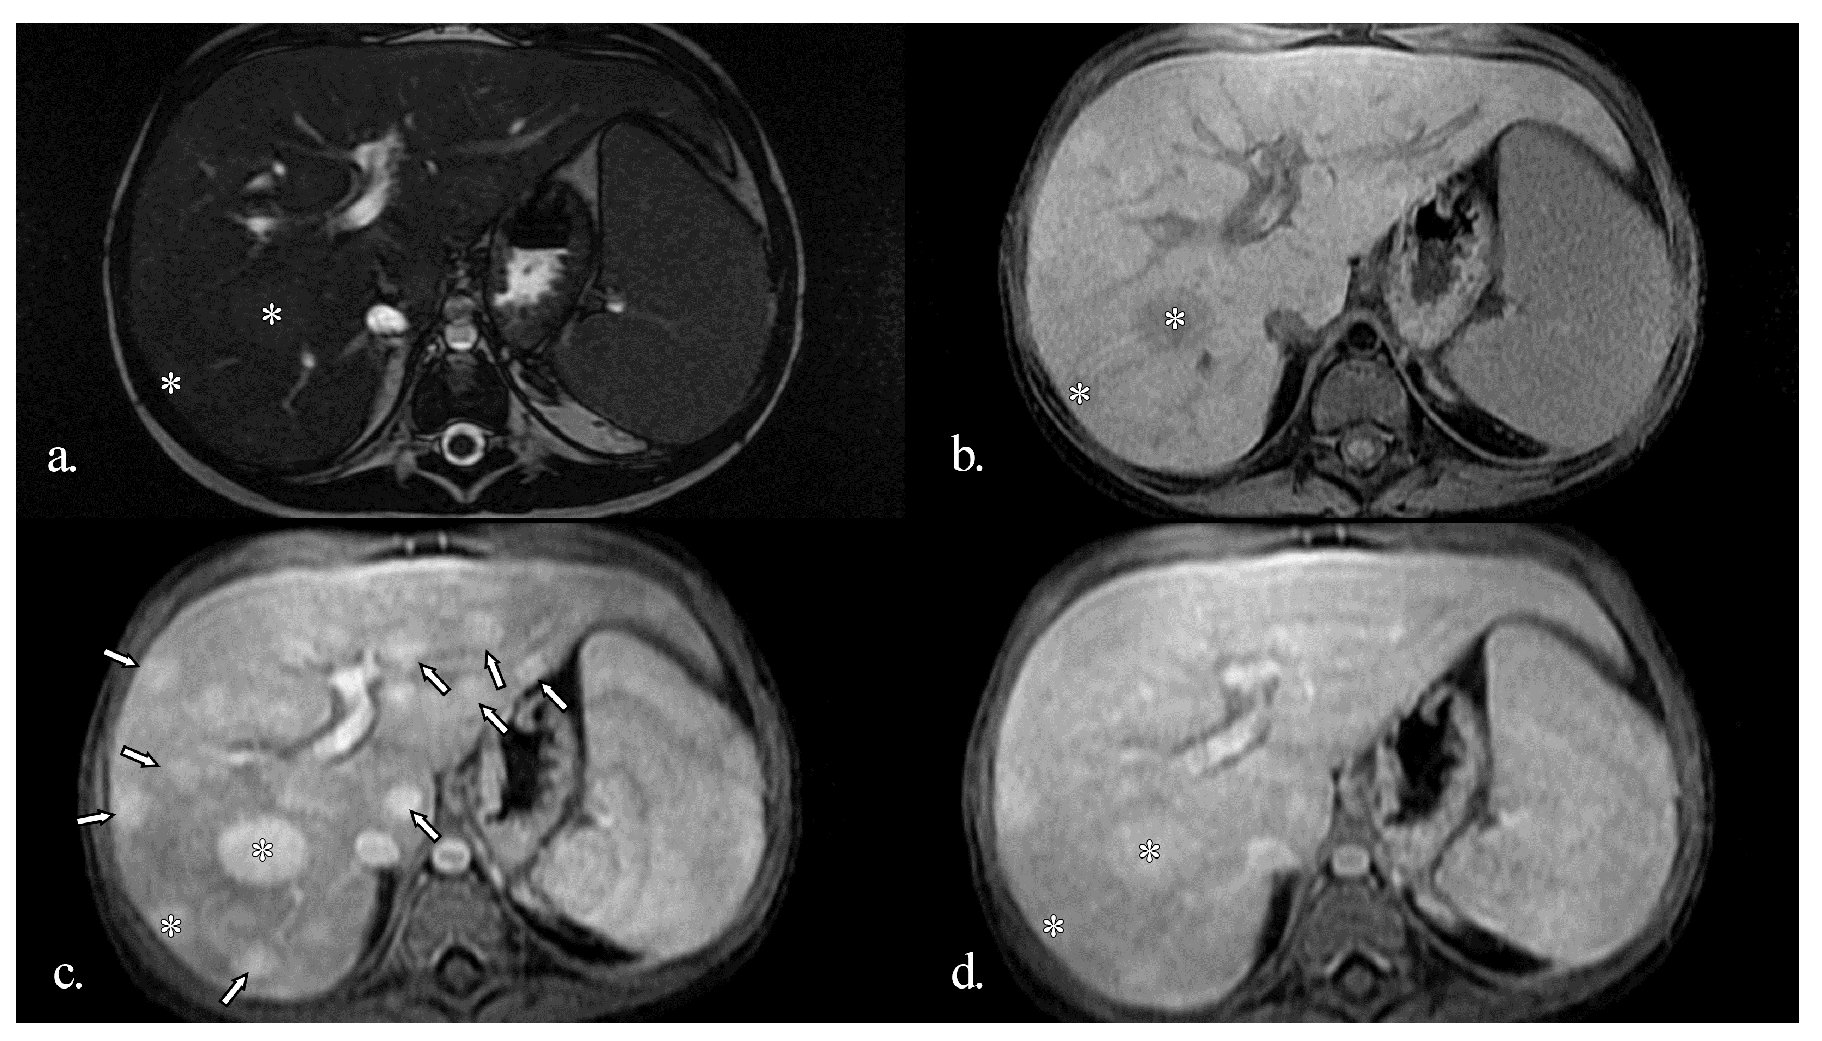

At 5.5 years of age, ultrasound revealed multiple diffuse hyperechoic hepatic lesions measuring 1–2 cm and mild splenomegaly. On contrast-enhanced ultrasound (CEUS), the lesions exhibited arterial-phase hyperenhancement with centrifugal filling and became isoenhancing during the portal and late phases (Figure 1). These features were interpreted as consistent with large regenerative nodules of focal nodular hyperplasia-like appearance (FNH-like). At this stage, serum GGT levels were elevated and remained persistently high, peaking at 120 U/L. Serum transaminases (AST and ALT) were only slightly elevated, with ALT sometimes remaining within the normal range.

Figure 1. Initial ultrasound (US) of the liver before treatment. (a) Grey-scale US showing a hyperechoic nodule in the right lobe; (b) Contrast-enhanced ultrasound (CEUS). Arterial phase. Multiple round hyperenhancing nodules in the right lobe (marked with the symbol ‘>’ on the image); (c) CEUS in parenchymal phase. The nodules are isoenhanced and no longer detectable.

Grey-scale ultrasound detection of NRH is challenging, particularly for an inexperienced sonographer, because nodules are usually small and commonly isoechoic, and they affect the entire hepatic parenchyma diffusely. Moreover, in our patient, many larger nodules were identified with CEUS, highlighting its additional value in evaluating such cases.

Contrast-enhanced ultrasound has been sporadically explored for evaluating NRH. Evidence is limited to isolated case reports [21]. Due to the diffuse and micronodular nature of NRH, the technique lacks sensitivity and specificity. CEUS may occasionally reveal non-specific or misleading enhancement patterns, so its findings should always be interpreted in conjunction with clinical data, cross-sectional imaging, and histopathological confirmation. Currently, no validated CEUS criteria are available for the identification of NRH.

Larger hepatic lesions, such as those resembling focal nodular hyperplasia (FNH), can be more accurately characterised using CEUS. These lesions typically exhibit intense centrifugal arterial-phase enhancement, followed by isoechoic enhancement during the portal venous and delayed phases [22]. The development of advanced CEUS techniques, together with higher-resolution contrast agents and emerging microbubble or molecular contrast media, is expected to improve the detection and characterisation of microvascular alterations seen in nodular regenerative hyperplasia (NRH).

In our patient, CEUS provided additional value in characterising the hepatic lesions. The presence of larger, hyperenhancing nodules with centrifugal arterial-phase filling and isoenhancement in the portal and late phases was consistent with FNH-like regenerative nodules. Depending on the clinical context, however, malignant lesions should be considered in the differential diagnosis.